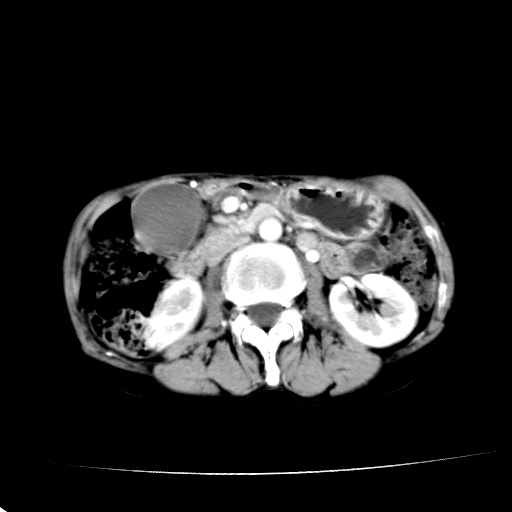

以下是引用dyqct在2008-6-3 14:54:00的发言:[br]支持 胰头癌伴肝内外胆管扩张,胰管扩张,胰头增大,增强见结节状轻度强化影,双管征明显。肠系膜上静脉已受侵(已不能手术),建议离子植入治疗吧。